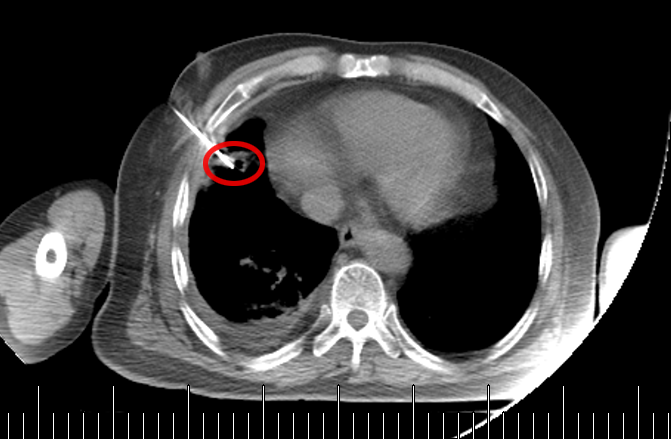

起初,常规思路是做气管镜检查取病理,但完善肺功能检查后发现,老先生有重度阻塞性肺通气功能障碍(相当于呼吸系统 “交通堵塞”),根本耐受不了气管镜。好在这个肿块虽然位置特殊,但体积较大、离胸壁较近 —— 和患者及家属充分沟通后,医生决定采用 “CT 引导下经皮肺穿刺活检”。

操作很快完成,术中术后都没有出现血气胸,老先生精神状态良好,也没觉得胸闷胸痛。3 天后病理报告出来了:小细胞癌!原来这不是结肠癌肺转移,而是老爷爷患上了第二种原发肿瘤,是肺里地地道道的 “原住民”。